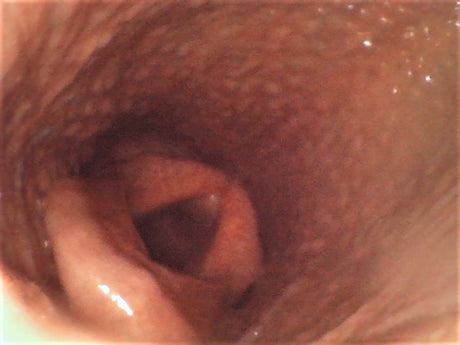

YE-80150M-28 Joystick Articulation Veterinary Endoscope 8mm Diameter 1.5m Probe 4.5" Monitor